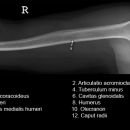

Oberarm a.-p. (1. Ebene)

Beurteilungskriterien

- Ellenbogenaxialwinkel = 162°

- Gelenkspaltbreite (Ellenbogengelenk) = 3mm

Täuschungen

- bei Ruptur der Gelenkkapsel/RM kommt es durch den Muskelzug zu Rotationsdislokation, die eine Gelenkluxation vortäuschen können.

- Durch posttraumatische Ruhigstellung können durch den Verlust des Muskeltonus Humeruskopfluxationen nach kaudal vorgetäuscht werden.